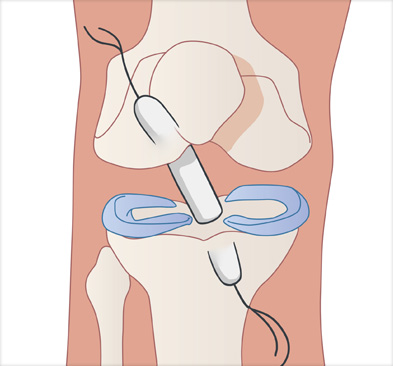

십자인대 재건술은 손상된 인대를 자가건이나 타가건을 활용해 원래의 인대의 위치에 재건하여 무릎의 기능을 회복시킵니다.

이식할 인대 삽입

이식한 인대 고정